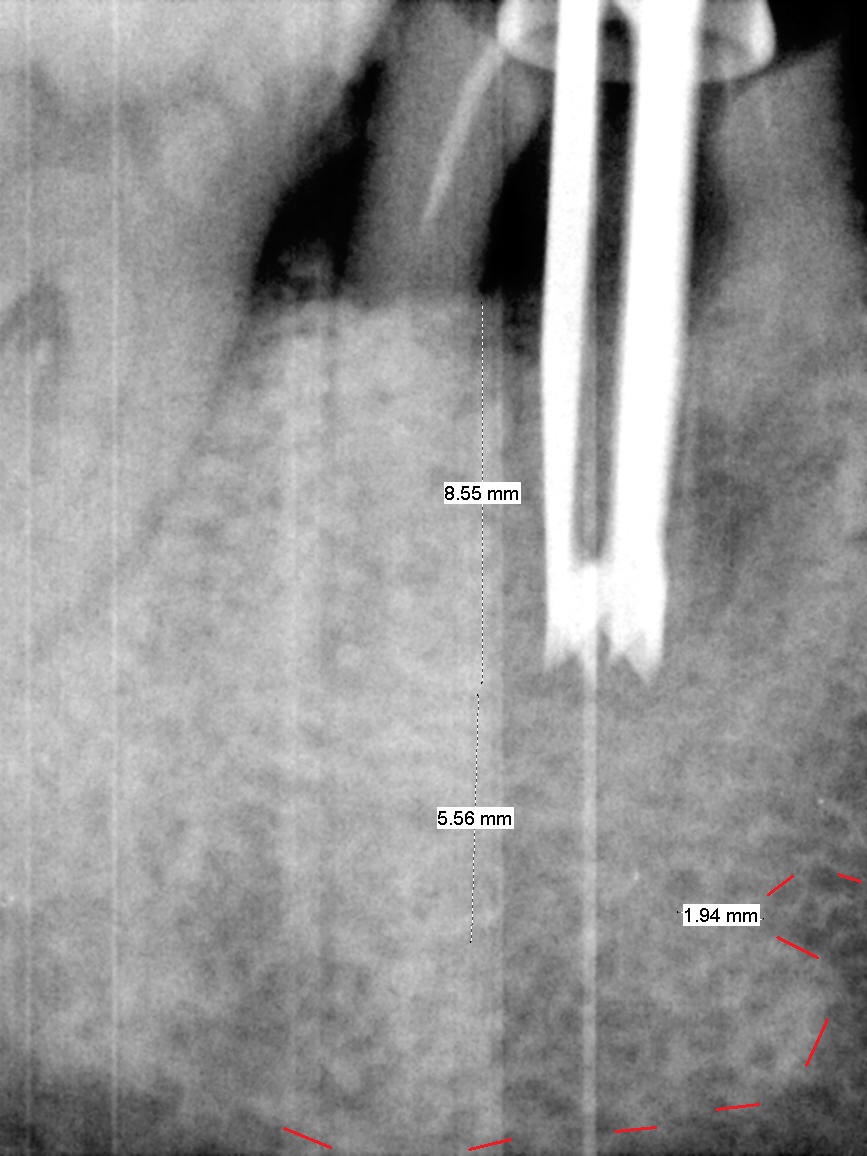

After cleaning the root surface with a surgical curette, a 1.6 mm pilot drill is used to start osteotomy (O) between the mesial (M) and distal (D) roots, followed by a marking bur and 3.8 mm Magic drill 13 mm deep (Fig.1,2). Following root removal, the 3.8 mm drill is reused for 11 mm (Fig.3). After deepening the osteotomy for another 2 mm, a 4.5x13 mm implant is placed with insertion torque of 50 Ncm, followed by allograft (*, .5-2 mm) and a 5x4(2) mm abutment (Fig.4,5). An immediate provisional is fabricated to close the socket (Fig.6 P (lock in)). The detached buccal gingiva (Fig.6 *) is kept in place by applying periodontal dressing (Fig.7 *). Red dashed lines in Fig.1, 3, 5 represents the superior border of the Inferior Alveolar Canal and Mental Foramen.